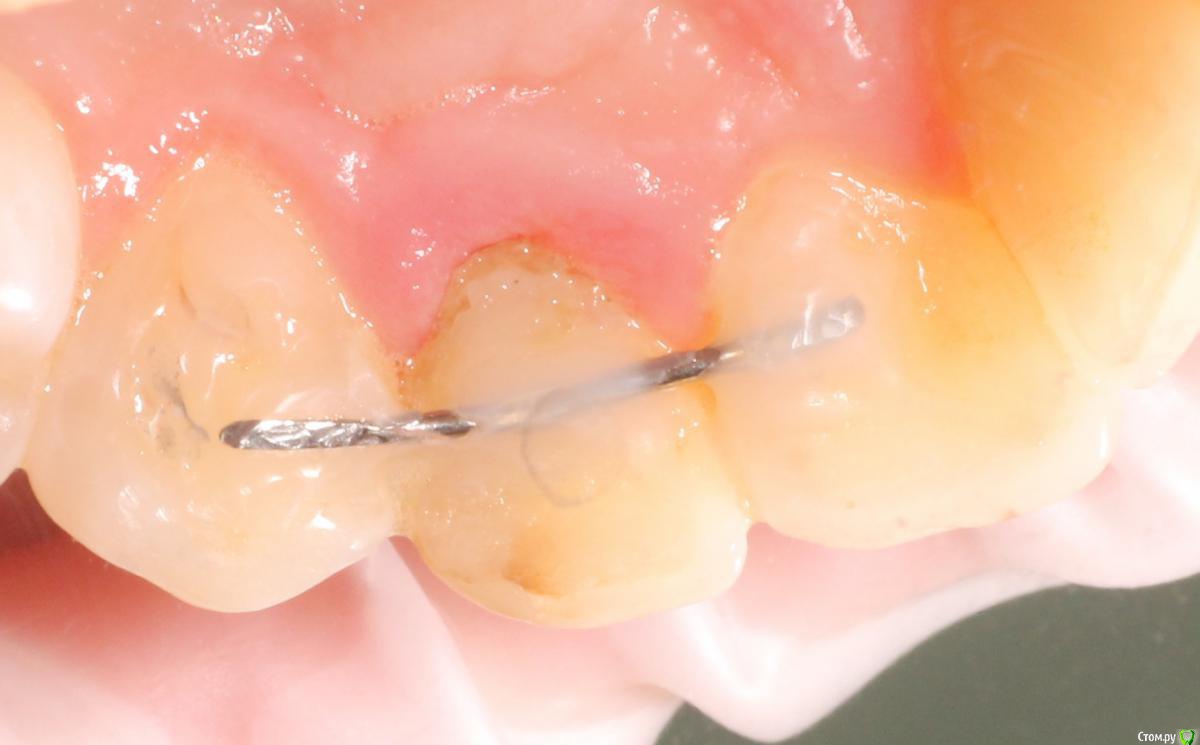

MenshikovDV Опубликовано 2 апреля, 2015 Поделиться Опубликовано 2 апреля, 2015 (изменено) Зуб 1.2 отлом коронковой части зуба, на период ожидания приема у хирурга и ортопеда (2 дня) приклеен к соседям. Вся процедура в одно посещение. Где-то часа два. Я ортопед, хирургия не моя, фото мои Изменено 2 апреля, 2015 пользователем MenshikovDV 19 Ссылка на комментарий

Brigita Опубликовано 5 апреля, 2015 Поделиться Опубликовано 5 апреля, 2015 на удаленном зубе какая то железячка хвостиком торчит))) Ссылка на комментарий

MenshikovDV Опубликовано 7 апреля, 2015 Автор Поделиться Опубликовано 7 апреля, 2015 ИНСТРУМЕНТ сломан в канале )) Ссылка на комментарий